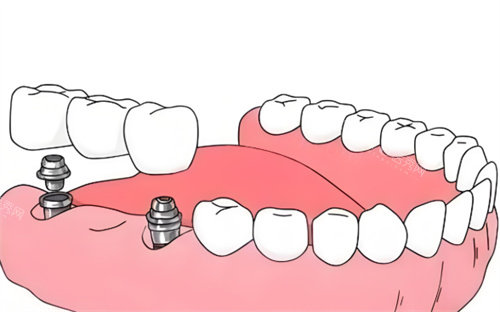

种植牙项目

百康特种植体:3000元起

奥齿泰种植体:5800元起

瑞士ITI种植体:12800元起

诺贝尔种植体:15800元起